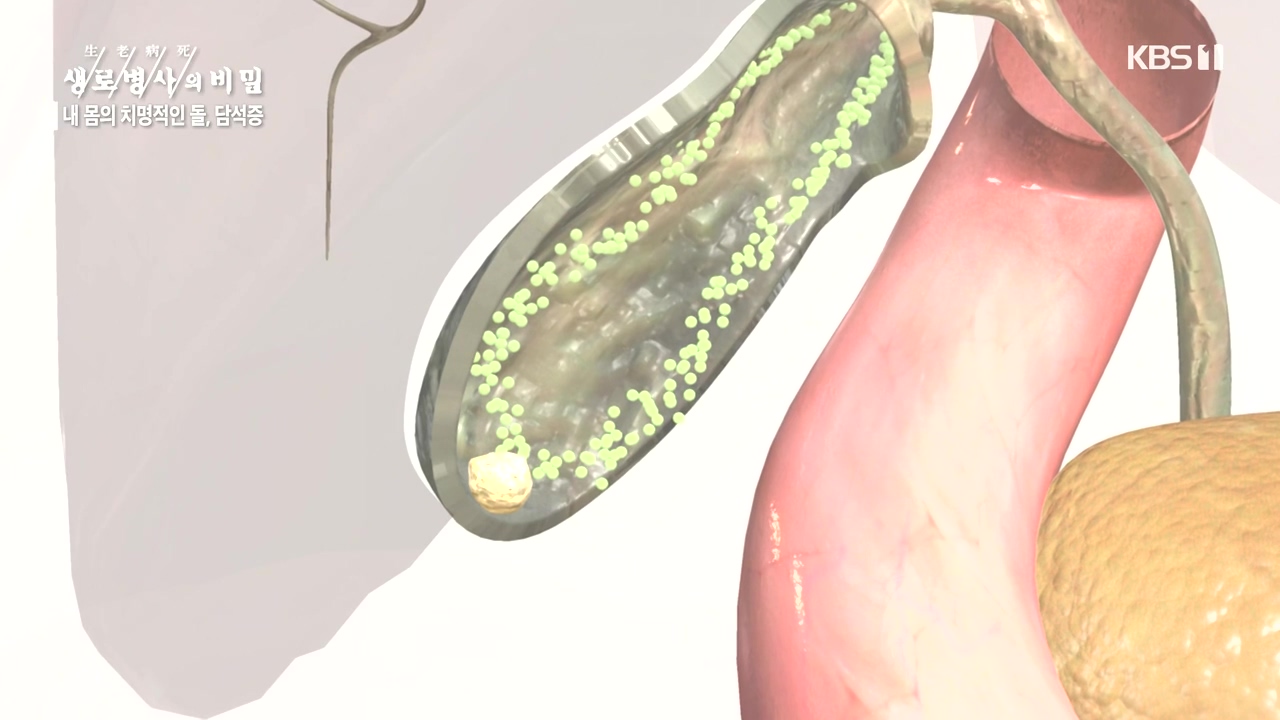

[박은철 기자] 담석증은 지방 소화를 돕는 담낭(쓸개)에 담즙이 굳어서 돌처럼 덩어리가 생기는 질환이다. 주로 쓸개주머니라 불리는 담낭 안이나...

내 몸의 치명적인 돌 담석증